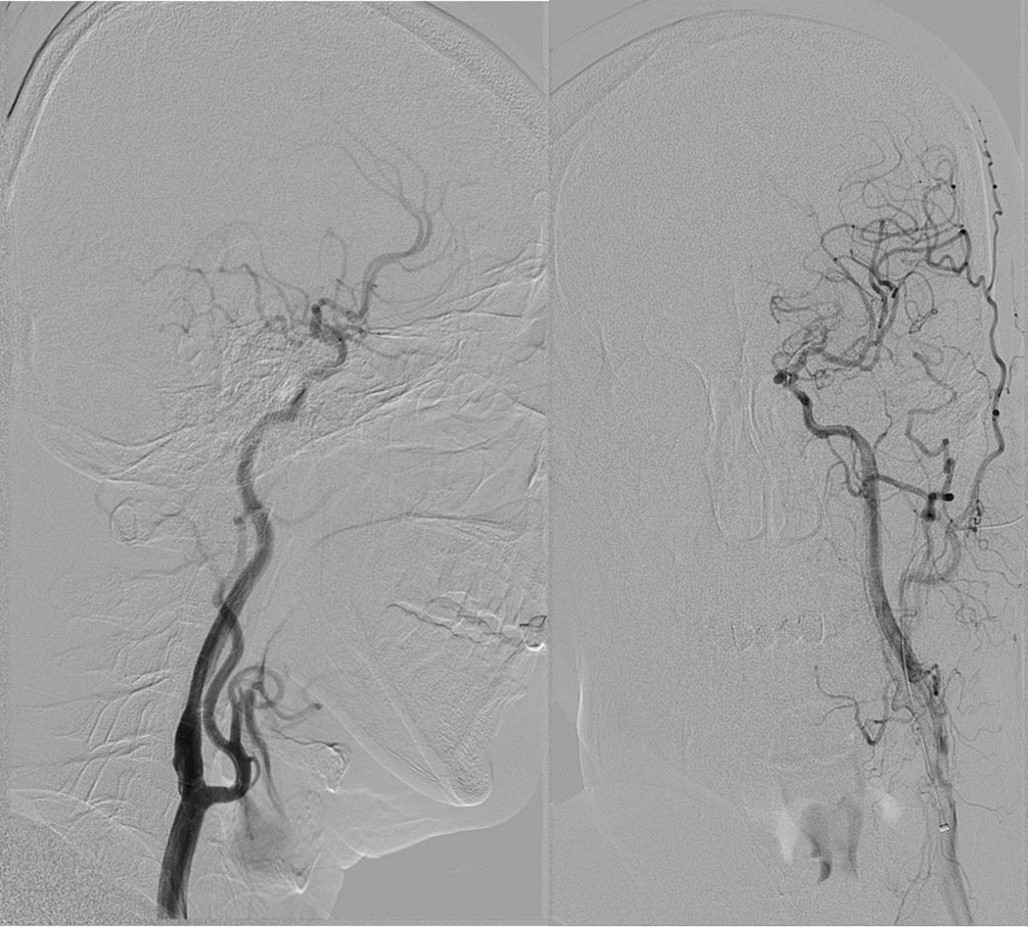

清华长庚血管外科 9月8日(通讯员 赵克强 吴巍巍)王先生今年50岁,头晕、黑矇反复发作,1周前超声发现左侧颈动脉狭窄,赶紧就诊于清华长庚医院,颈动脉CTA发现王先生的左侧颈内动脉起始端粥样硬化斑块形成、重度狭窄,病变位置很高,更复杂的是还同时合并颈总动脉起始部狭窄(图1、2)。入院后血管外科医生为王先生进行了全面的颈动脉斑块性质评估:超声造影检查发现斑块内线样增强提示斑块内新生血管;斑块MRI分析均提示斑块内出血。上述评估均提示该斑块可能为不稳定斑块,极易脱落导致脑梗死,头颅核磁也证实了左侧颈动脉供血区域大脑半球多发腔隙性梗塞。结合王先生的症状、狭窄程度以及斑块不稳定性质,进行斑块剥离手术或微创支架手术的指证明确,由于CTA提示颈动脉狭窄病变很高,剥离手术风险高,我们决定为王先生施行微创手术。

术前CTA提示王先生的主动脉弓形为“牛”型解剖变异(左侧颈总动脉从无名动脉发出,图1),颈总动脉起始部及颈内动脉均存在斑块狭窄,为手术增加了难度,经过仔细讨论分析病情,血管外科吴巍巍主任、赵克强教授决定“另辟蹊径”,从患者右上肢入路,实施微创颈动脉支架手术,同期解决颈总及颈内动脉两处病变。经过充分的术前准备,吴巍巍主任和赵克强教授在麻醉科医师的保驾下联手为王先生安全实施颈动脉微创支架植入术(图3、4),避免了王先生今后再次发生严重的脑卒中事件。术后返回病房,精准调控血压、心率,5天后王先生顺利康复出院。

图1 颈动脉狭窄病变很高合并颈总动脉狭窄合并牛型弓